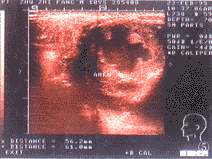

1例假性动脉瘤的CDFI的特征见图4(封四)。

图4 左颈部假性动脉瘤,LECA示左颈外动脉

采用彩色血流显像检查肿块有助于了解肿块内的供血以及与周围大血管的关系,了解颈部如颈总动脉、颈内动脉和颈外动脉以及颈静脉等大血管的走向,肿瘤有无浸润,避免损伤重要的血管。图4为1例左颈部颈外动脉假性动脉瘤,B超检查中我们非常直观地看到颈外动脉每次搏动均将血喷入瘤体中,并形成涡流,瘤体位于距颈内、外动脉分叉处2.2 cm,我们在术中能结扎颈外动脉而不损伤颈总动脉或颈内动脉,患儿痊愈。术后多次复查未见异常。图5为术后1个月复查之血流显像,未见患侧颈外动脉血流信号,假性动脉瘤体机化,无血流信号。